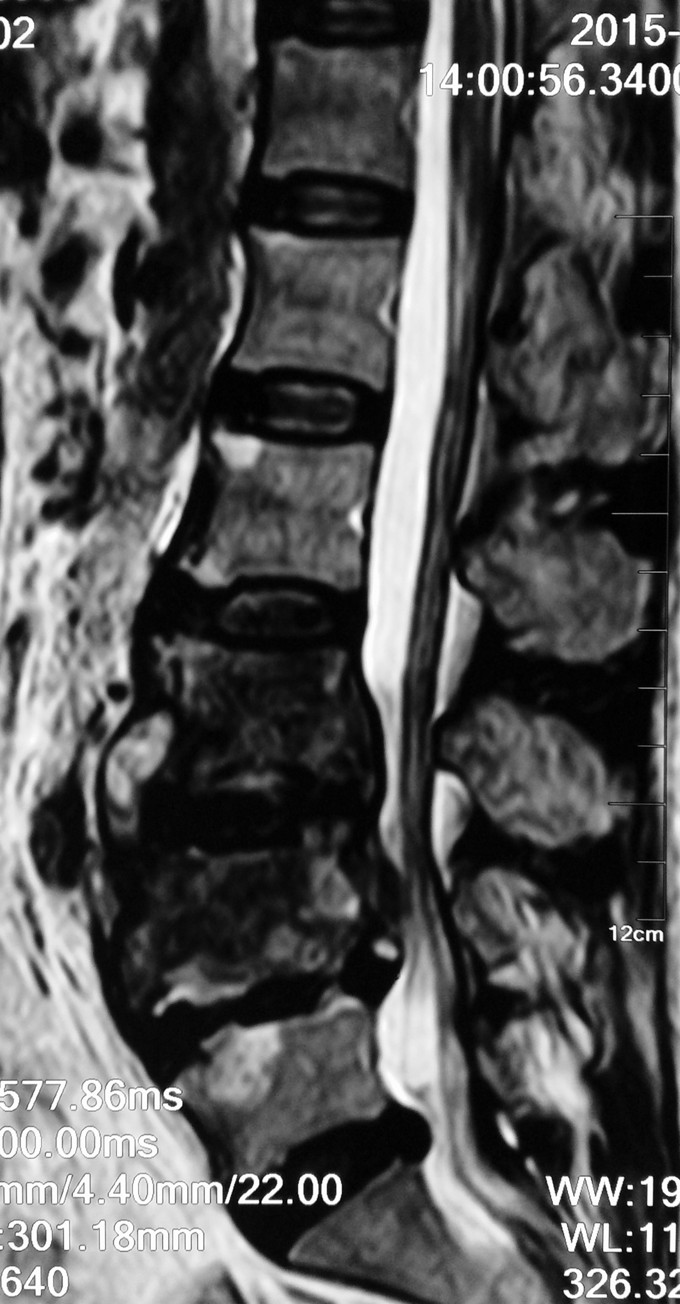

患者女性,58岁。 腰痛间断性发作2年,加重伴左下肢疼痛不适4月 疼痛以久坐和劳累后症状明显,近4月上述症状加重,伴有左下肢麻木疼痛感,经卧床休息后不能缓解。

腰3-4/4-5间隙及椎板压痛及叩击痛,无明显下肢放射痛。左大腿前外侧及膝以下感觉有减退,左侧髋、膝肌力5级,拇趾背伸肌力4级,肌张力不高,左下肢直腿抬高试验40°阳性,加强试验阳性。右下肢感觉肌力正常。 血沉 99mm/h C反应蛋白:4.1ng/L 斑点试验:抗A 111,kangB 127

1.腰3-4结核 2.腰4-5椎管狭窄 因术前血沉比较高,所以予以HREZS抗痨治疗2周,血沉至44mm/h,患者一般情况较前好转。安排手术治疗:后路腰3-4椎间病灶清除椎板植骨+腰4-5减压植骨内固定融合术。

此患者腰椎结核伴有相邻节段椎管狭窄,所以兼有两者的症状。对于此病例我们考虑因患者椎体前方脓肿不明显,所以考虑一起行后方椎间隙病灶清除,植入自体椎板骨融合内固定,同时进行腰4-5后路减压内固定融合术。 不知大家对结核的病人一般是通过何种方式进行病灶清除的?选择原则是什么?